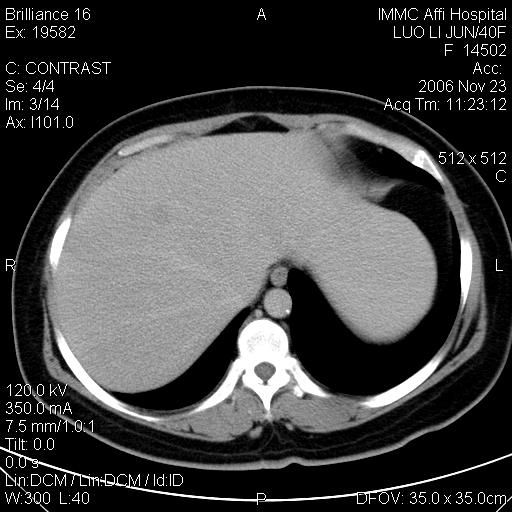

标题: CT5664:我也发一个肝脏的片子大家看看

很典型的肝癌。

速升速降,典型肝癌.

是啊,典型的早出早归!

快进快出典型肝癌.

符合肝癌的增强特征。支持肝癌!

很好的片子,可惜增强做的比较失败,a期时间没有把我好,实际到了静脉早期了,否则会更典型。

最终考虑是肝腺瘤